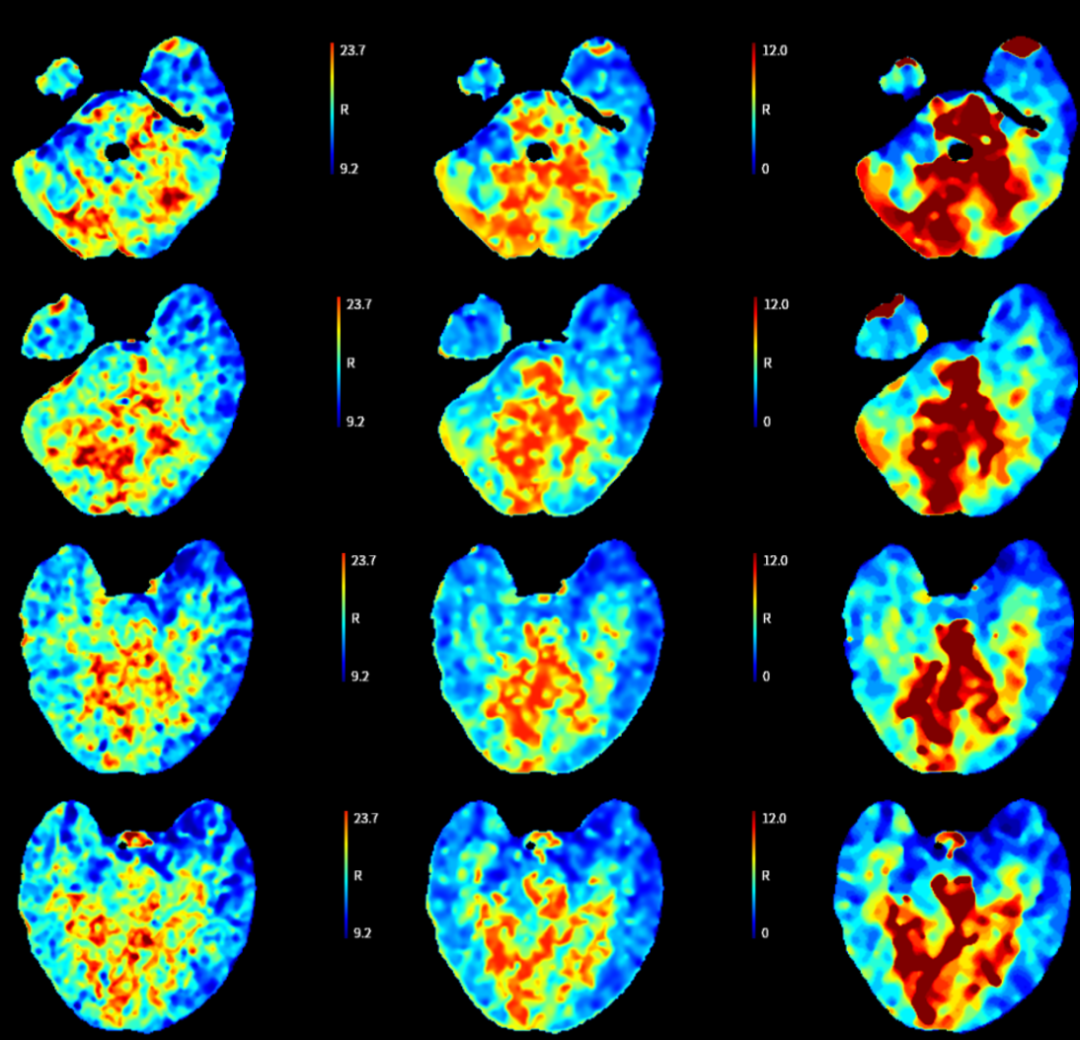

➢头颈部CTA+脑灌注

-

双侧枕叶、丘脑、脑干及双侧小脑半球血流灌注减低,建议MRI检查。

双侧椎动脉V4管腔闭塞,建议DSA检查。

双侧颈内动脉虹吸段钙化斑块,管腔中-重度狭窄;双侧大脑中动脉M1段、大脑后动脉硬化,管腔轻微-轻度狭窄。

双侧大脑前动脉共干。

患者为老年男性,病情进展加重快,入院时已超静脉溶栓时间窗,意识障碍逐渐加深,NIHSS评分:13分;头颅CT未见明显梗死病灶;头颈部CTA+脑灌注提示:双侧枕叶、丘脑、脑干及双侧小脑半球血流灌注减低,双侧椎动脉V4管腔闭塞。